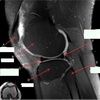

INFRASPINATUS MUSCLE

How well did you know this?

1

Not at all

2

3

4

5

Perfectly

10

Q

What is letter D?

A

GLENOID

11

What is letter A?

ANTERIOR LABRUM